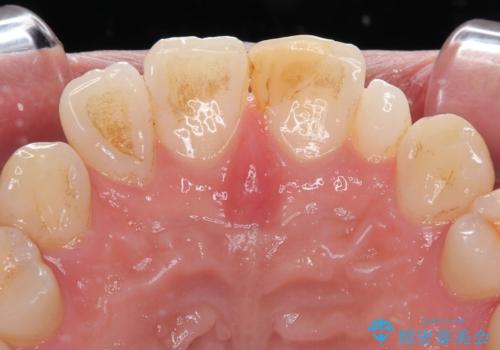

- 隙間を埋めた材料の変色や形を気にして来院された患者様です。

矯正治療などを含めて治療方法を相談した結果、当該歯をオールセラミッククラウンにて補綴治療を行うこととしました。

前歯の単独歯の補綴治療であったので、オーダーメイドタイプをおすすめしましたが、今回は既製タイプにて製作を進めました。